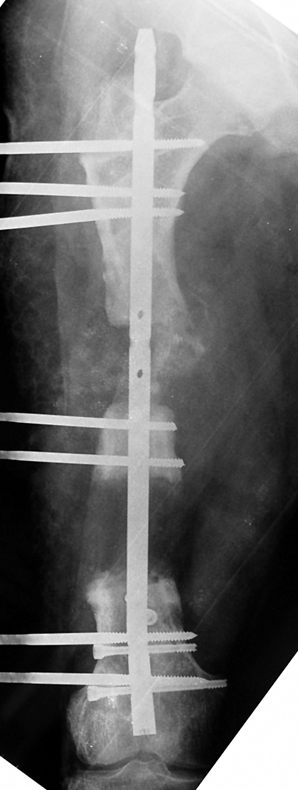

The duration of external fixation (external fixation index) depends on the amount of distraction required, and the extremity is prone to complications during this period. After the distraction phase is completed, the external fixator remains in place during the consolidation phase, which lasts twice as long as the distraction phase; but this period is hardly tolerated. If the external fixator is removed before sufficient consolidation is achieved, fractures, deformity and shortness will be the result. In our department, ‘lenghthening over nail’ method is used in order to decrease the external fixation index and increase patient comfort and activity level. In this method, the intramedullary nail is statically locked after the completion of the distraction phase, and external fixator is removed. The extremity is stabilized by the intramedullary nail during consolidation phase. In this way, complications due to long external fixation index or early removal of the external fixator are avoided.

Case 2